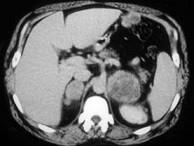

问题 男,56岁,有恶性黑色素瘤病史,请结合图像,作出诊断()

选项 A.肾上腺腺瘤 B.肾上腺髓样脂肪瘤 C.肾上腺癌 D.肾上腺转移瘤 E.肾上腺嗜铬细胞瘤

答案 D